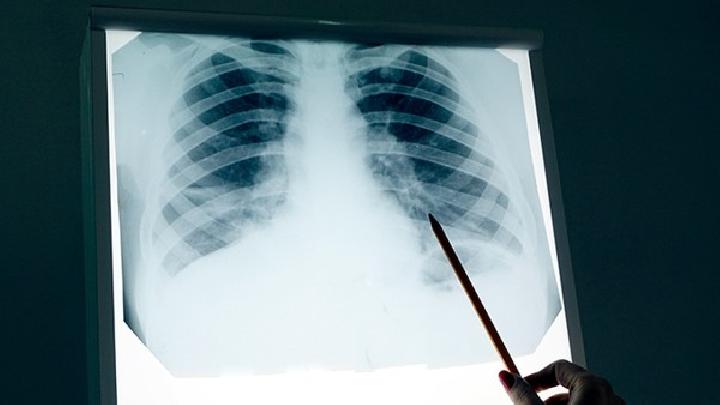

无论什么疾病,越早发现越好,肺纤维化也不例外。许多肺纤维化患者在早期无法发现,因为他们不了解自己的疾病。因此,如果你想在早期发现它,了解它的临床表现是必不可少的。

读完以上内容后,我们应该了解肺纤维化的症状。一旦发现有相关异常,必须立即到正规医院进行诊断和治疗,以免延误病情。在这里,祝你一切顺利!